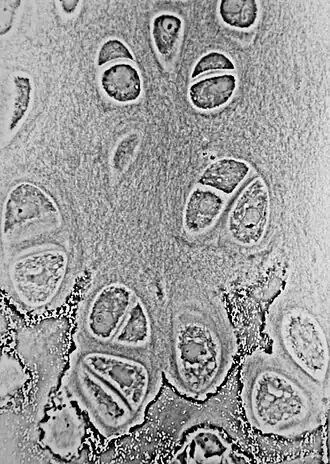

![]() Light micrograph of undecalcified hyaline cartilage showing its chondrocytes and organelles, lacunae and matrix. | |

The chondrocyte in cartilage matrix has rounded or polygonal structure. The exception occurs at tissue boundaries, for example the articular surfaces of joints, in which chondrocytes may be flattened or discoid. Intra-cellular features are characteristic of a synthetically active cell. The cell density of full-thickness, human, adult, femoral condyle cartilage is maintained at 14.5 (±3.0) × 103 cells/ mm2 from age 20 to 30 years. Although chondrocyte senescence occurs with aging, mitotic figures are not seen in normal adult articular cartilage. The structure, density, and synthetic activity of an adult chondrocyte are various according to its position. Flattened cells are oriented parallel to the surface, along with the collagen fibers, in the superficial zone, the region of highest cell density. In the middle zone, chondrocytes are larger and more rounded and display a random distribution, in which the collagen fibers also are more randomly arranged. In the deeper zones, chondrocytes form columns that are oriented perpendicular to the cartilage surface, along with the collagen fibers. Different behaviors may be exhibited by chondrocytes depending on their position within the different layers. In primary chondrocyte cultures, these zonal differences in synthetic properties may persist. The primary cilia are significant for spatial orientation of cells in developing growth plate and are sensory organelles in chondrocytes. Primary cilia work as centers for wingless type (Wnt) and hedgehog signaling and contain mechanosensitive receptors.[3]